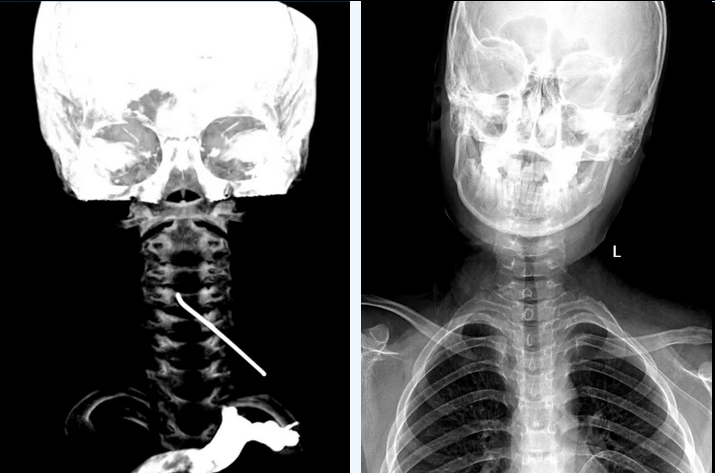

这名来自新疆的男孩儿颈部剧烈疼痛、活动严重受限,一家人辗转多地后,慕名找到北京协和医院神经外科高俊副主任。孩子的检查结果令人揪心:一枚长约10cm的金属异物从椎间孔斜行插入颈椎管内,尖端还带有一段弯钩,如同一颗随时可能引爆的“定时炸弹”。追问病史发现,患儿曾因左侧锁骨骨折,在当地接受“骨折复位内固定”手术。

▲术前可见金属异物穿入颈椎管内(左图);术后可见颈部异物已拔除(右图)